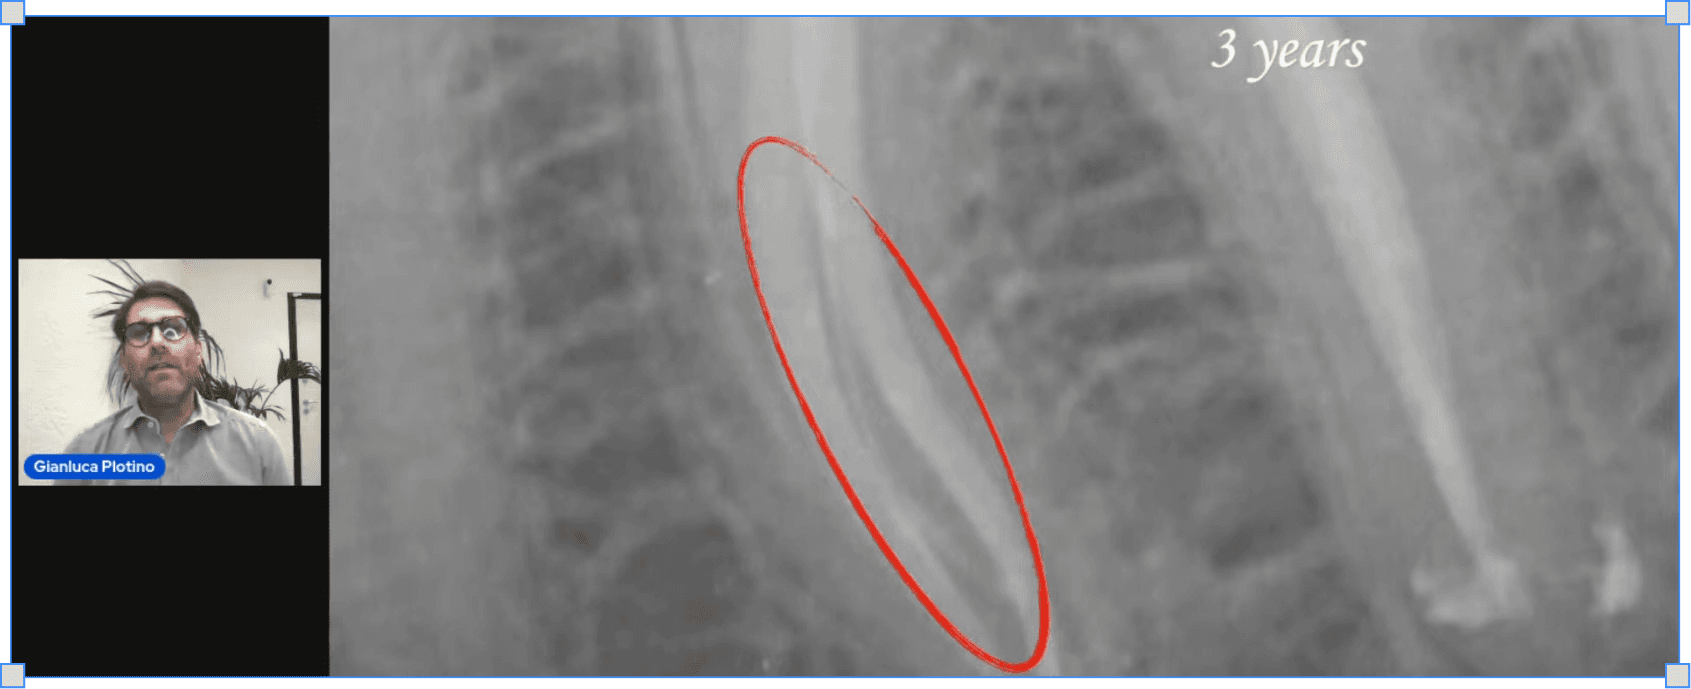

Gianluca Plotino

Протоколи іригації каналів

Все про іриганти та їх властивості. Протоколи активації

Все про роботу ендодонтиста зі змазаним шаром

Покроковий протокол дезінфекціїх кореневих каналів

Станіслав Геранін

Все про

резорбції

Сучасна класифікація резорбтивних уражень

Основні критерії оцінки прогнозу та методів лікування

Лікування перфоруючих внутрішніх та комбінованих резорбцій